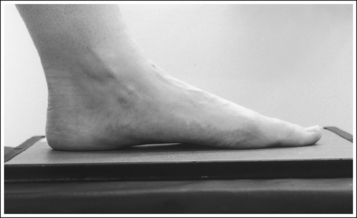

• Determining required obliquity. To determine whether a 30- or 60-degree rotation is needed, view the medial aspect of the patient's foot in an AP projection to judge the height of the patient's longitudinal arch. Less obliquity is required in a patient with a low longitudinal arch than in a patient with a high arch. If the patient has a low arch (Figure 6-20; also see Figure 6-15), rotate the patient's foot approximately 30 degrees medially; if the patient's foot has an average arch (Figure 6-21; also see Figure 6-16), rotate the foot approximately 45 degrees medially; and, if the patient's arch is high (Figure 6-22; also see Figure 6-17), rotate the foot approximately 60 degrees. The average arch requires 45 degrees of rotation. As the foot is rotated, keep the lower leg, ankle, and foot aligned to judge the degree of foot obliquity better.

The height of the longitudinal arch can be determined by measuring the amount of cuboid demonstrated posterior to the navicular bone. The average lateral foot projection demonstrates approximately 0.5 inch (1.25 cm) of the cuboid, as shown in Figure 6-23. Because the bones that form the foot arch are held in position by ligaments and tendons, weakening of these tissues may result in a decreased or low arch. On a lateral foot projection, this decrease in arch height is demonstrated as a decrease in the amount of cuboid demonstrated posterior to the navicular bone. Figure 6-20 shows a lateral foot projection of a patient with a low longitudinal arch and approximately 0.25 inch (0.6 cm) of cuboid posterior to the navicular bone, whereas Figure 6-22 shows a patient with a high arch and approximately 0.75 inch (2 cm) of cuboid posterior to the navicular bone.